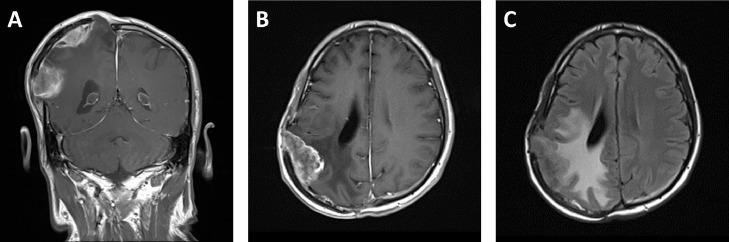

Meningiomas are common intracranial tumors that rarely metastasize. We present a highly unusual case of a 42-year-old man with direct seeding of meningioma to the abdominal wall. The patient had a history of multiple operations for a recurrent intracranial meningioma with decompressive craniectomy and preservation of the calvarial bone flap by implantation into the subcutaneous layer of the anterior abdominal wall. Following removal of the bone flap, a new abdominal wall mass was identified, consistent with iatrogenic implantation of anaplastic meningioma.

脑膜瘤是常见的颅内肿瘤,很少发生转移。我们报告一例极为罕见的病例,一名42岁男性,脑膜瘤直接播散至腹壁。该患者有多次复发性颅内脑膜瘤手术史,行减压颅骨切除术,并通过植入前腹壁皮下层保留颅骨骨瓣。在移除骨瓣后,发现一个新的腹壁肿物,符合间变性脑膜瘤的医源性植入。